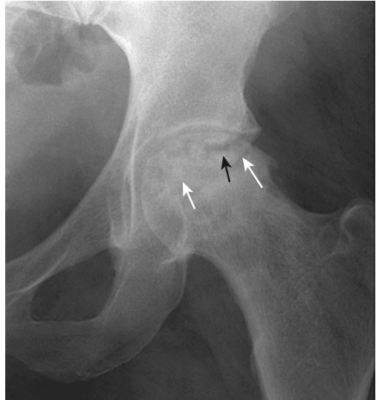

- Phần xương bị mất mạch máu trở nên đặc hơn và do đó có vẻ xơ cứng hơn phần xương còn lại. Điều này thấy rõ ở chỏm xương đùi (Hình-7) và chỏm xương cánh tay.